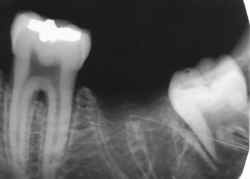

espaco2.gif (821 bytes)Radiografia do suspeito obtida intra-vitae e encaminhada ao IML pelo Cirurgião Dentista que cumpriu seu papel arquivando os exames complementares no prontuário odontológico.

espaco2.gif (821 bytes)Identificação positiva pela comparação computadorizada. Uma única radiografia intra-vitae como a comparada ao lado é suficiente para esta afirmação.

espaco2.gif (821 bytes)Entretando, o processo de identificação prossegue com a radiografia contralateral.

espaco2.gif (821 bytes)Observe as peculiaridades da imagem de radiodensidade metálica. Na verdade são duas restaurações cujas imagens se superpuseram, uma oclusal e outra vestibular.

espaco2.gif (821 bytes)Observe o número de cúspides do molar incluso.

espaco2.gif (821 bytes)O intervalo de tempo entre a radiografia intra-vitae e a época da morte calculada é compatível com a erupção ocorrida.